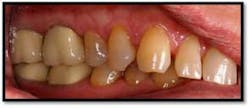

UL/LL Pre TxUL/LL Pre Tx reflected in a mirror